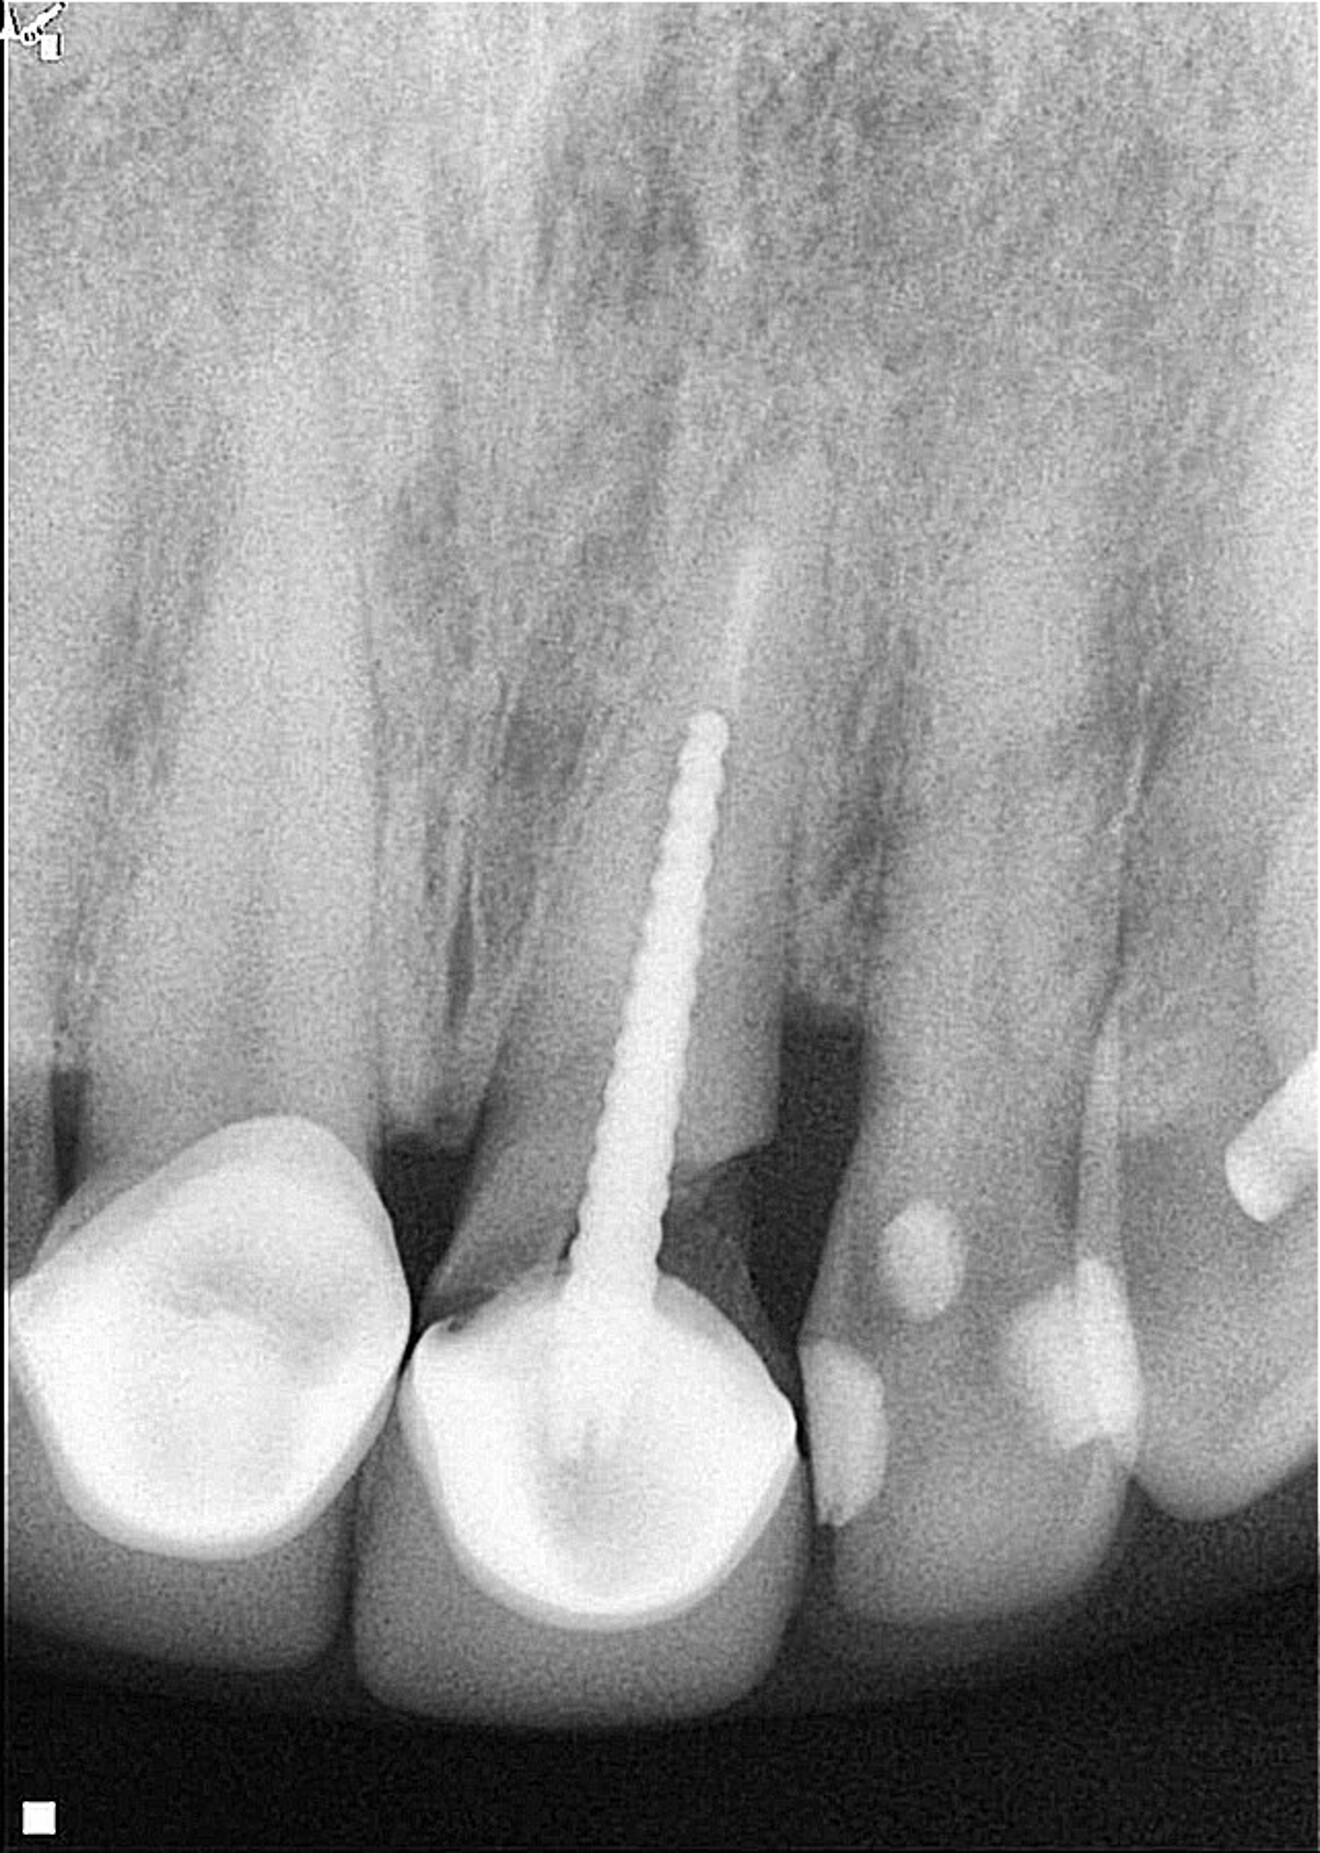

A female patient was evaluated in the dental office after a traumatic event involving her maxillary teeth. She had an oblique fracture from the mesial to distal aspect of the maxillary left central incisor at subgingival level, and the tooth’s metal post and metal–porcelain crown presented with mobility. The tooth had healthy periapical tissue (Fig. 1). Upon radiographic and clinical evaluation, it was noted that there was insufficient dental structure for a predictable restoration.15 Treatment planning included measurement and analysis of the root length, of the width of the root canal walls and of the available supragingival structure. Various treatment options were considered to save the tooth, and after a comprehensive evaluation, surgical extrusion was chosen as the preferred option to achieve adequate healthy supragingival dental structure, thereby offering the patient a favourable long-term treatment solution.6, 8

Fig. 1: Initial clinical radiograph showing tooth #21 with a previous root canal treatment, a metal post, a full-coverage coronal restoration and an oblique fracture from the mesial to distal aspect.